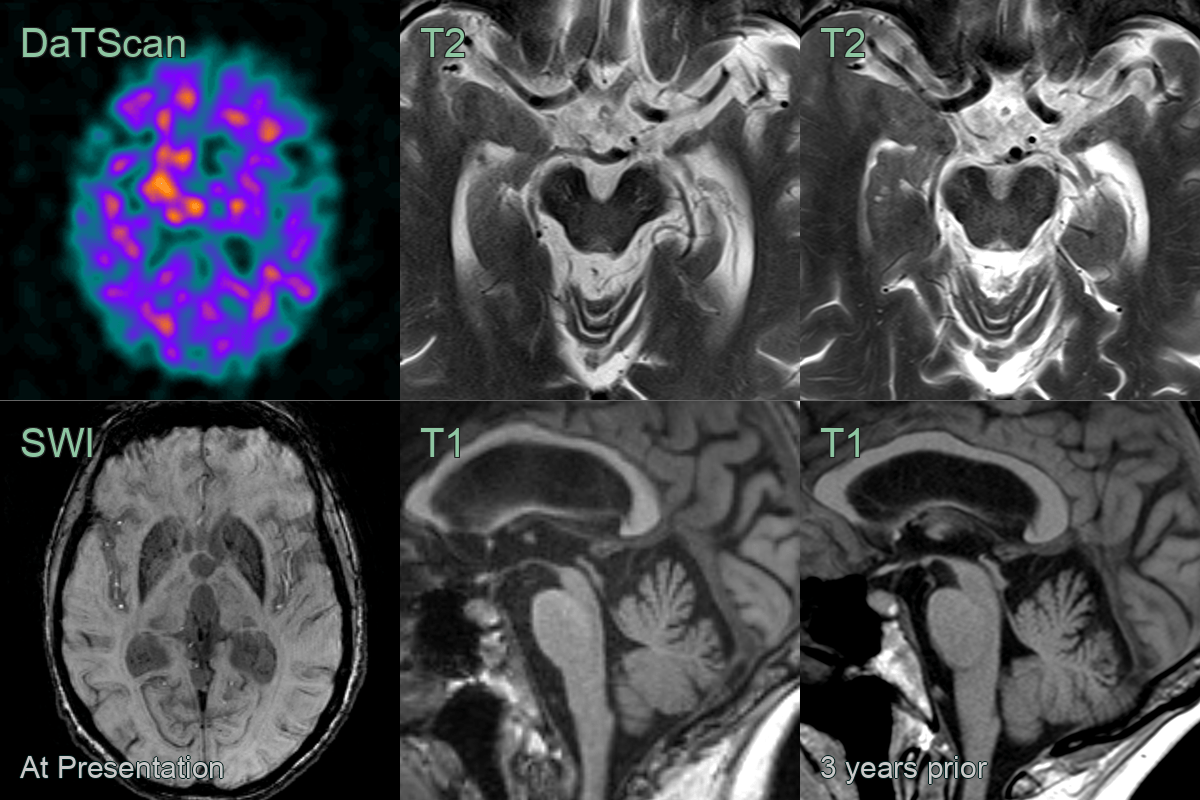

• 70-year-old patient presented with parkinsonism.

• MRI showed marked atrophy of the midbrain over a three year period.

• DaTscan showed high background uptake and with loss of the normal updake in the striatum.